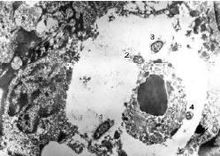

1、本病為慢性進行性病變,持續時間很長,有報導長達20—30年者,硬結病變極大多數原發於鼻腔前部,少數也可原發於咽、喉、氣管等處,出現相應的症狀,如耳鳴、耳聾、聲嘶、呼吸困難等。 2、活檢為診斷的主要依據,Mikulicz細胞和Russel小體為其特徵性表現,細菌培養可能查到鼻硬結桿菌,血清補體結合試驗也具有診斷價值。